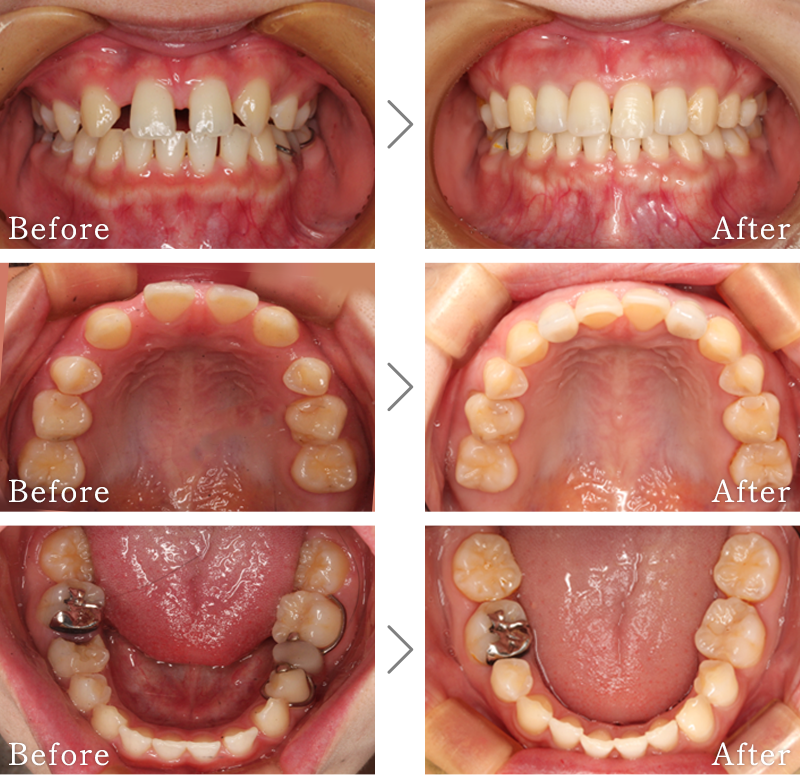

CASE5

主訴 前歯がグラグラして噛めないのと抜けそうで心配。

治療法 抜歯した後、歯周病で溶けて無くなってしまった骨を再生する手術とインプラント手術を同時に行なっています。

治療期間 8ヶ月

費用 CT:16,500円(税込)

+ インプラント治療:525,800円(税込)

+ 造骨処置:88,000円(税込)

合計:630,300円(税込)

副作用

• 歯周病に感染・発症し重度に進行するとインプラントが抜けてしまうことがあります。

• 手術後は数日間腫れが出る場合があります。

• 造骨処置を行なった部分に内出血などがあらわれる場合があります。